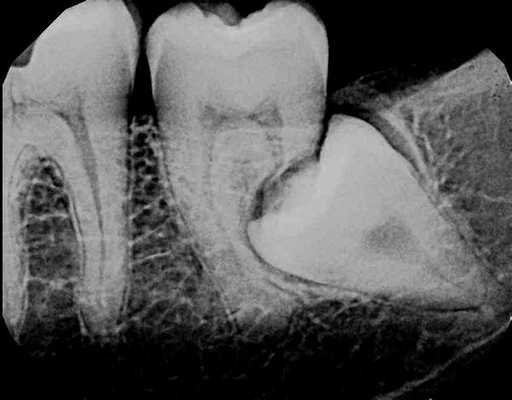

Классически предполагалось, что внутренняя резорбция витальных зубов развивается из-за травматического поражения пульпы (фото 1), а внешняя резорбция случается строго в девитальных зубах (фото 2). К последней могут привести травма периодонтальной связки вследствие воздействия внешних факторов, давления, которое возникает в результате прорезывания зубов, или же патологии развития (фото 3). Иногда внешняя резорбция наблюдается после проведенного ортодонтического лечения, которое провоцирует повышении активности остеокластов в области цемента и дентина верхушки корня. Большинство врачей конечно же полагаются на знания, полученные в ходе предварительного обучения, но некоторые все же интересуются динамикой развития доказательных фактов относительно тех или иных стоматологических патологий.

Фото 1. Рентгенограмма, демонстрирующая пример внутренней резорбции корня.

Фото 2. Рентгенограмма, демонстрирующая пример внешней воспалительной резорбции корня.

Фото 3. Рентгенограмма, демонстрирующая пример резорбции по причине давления.